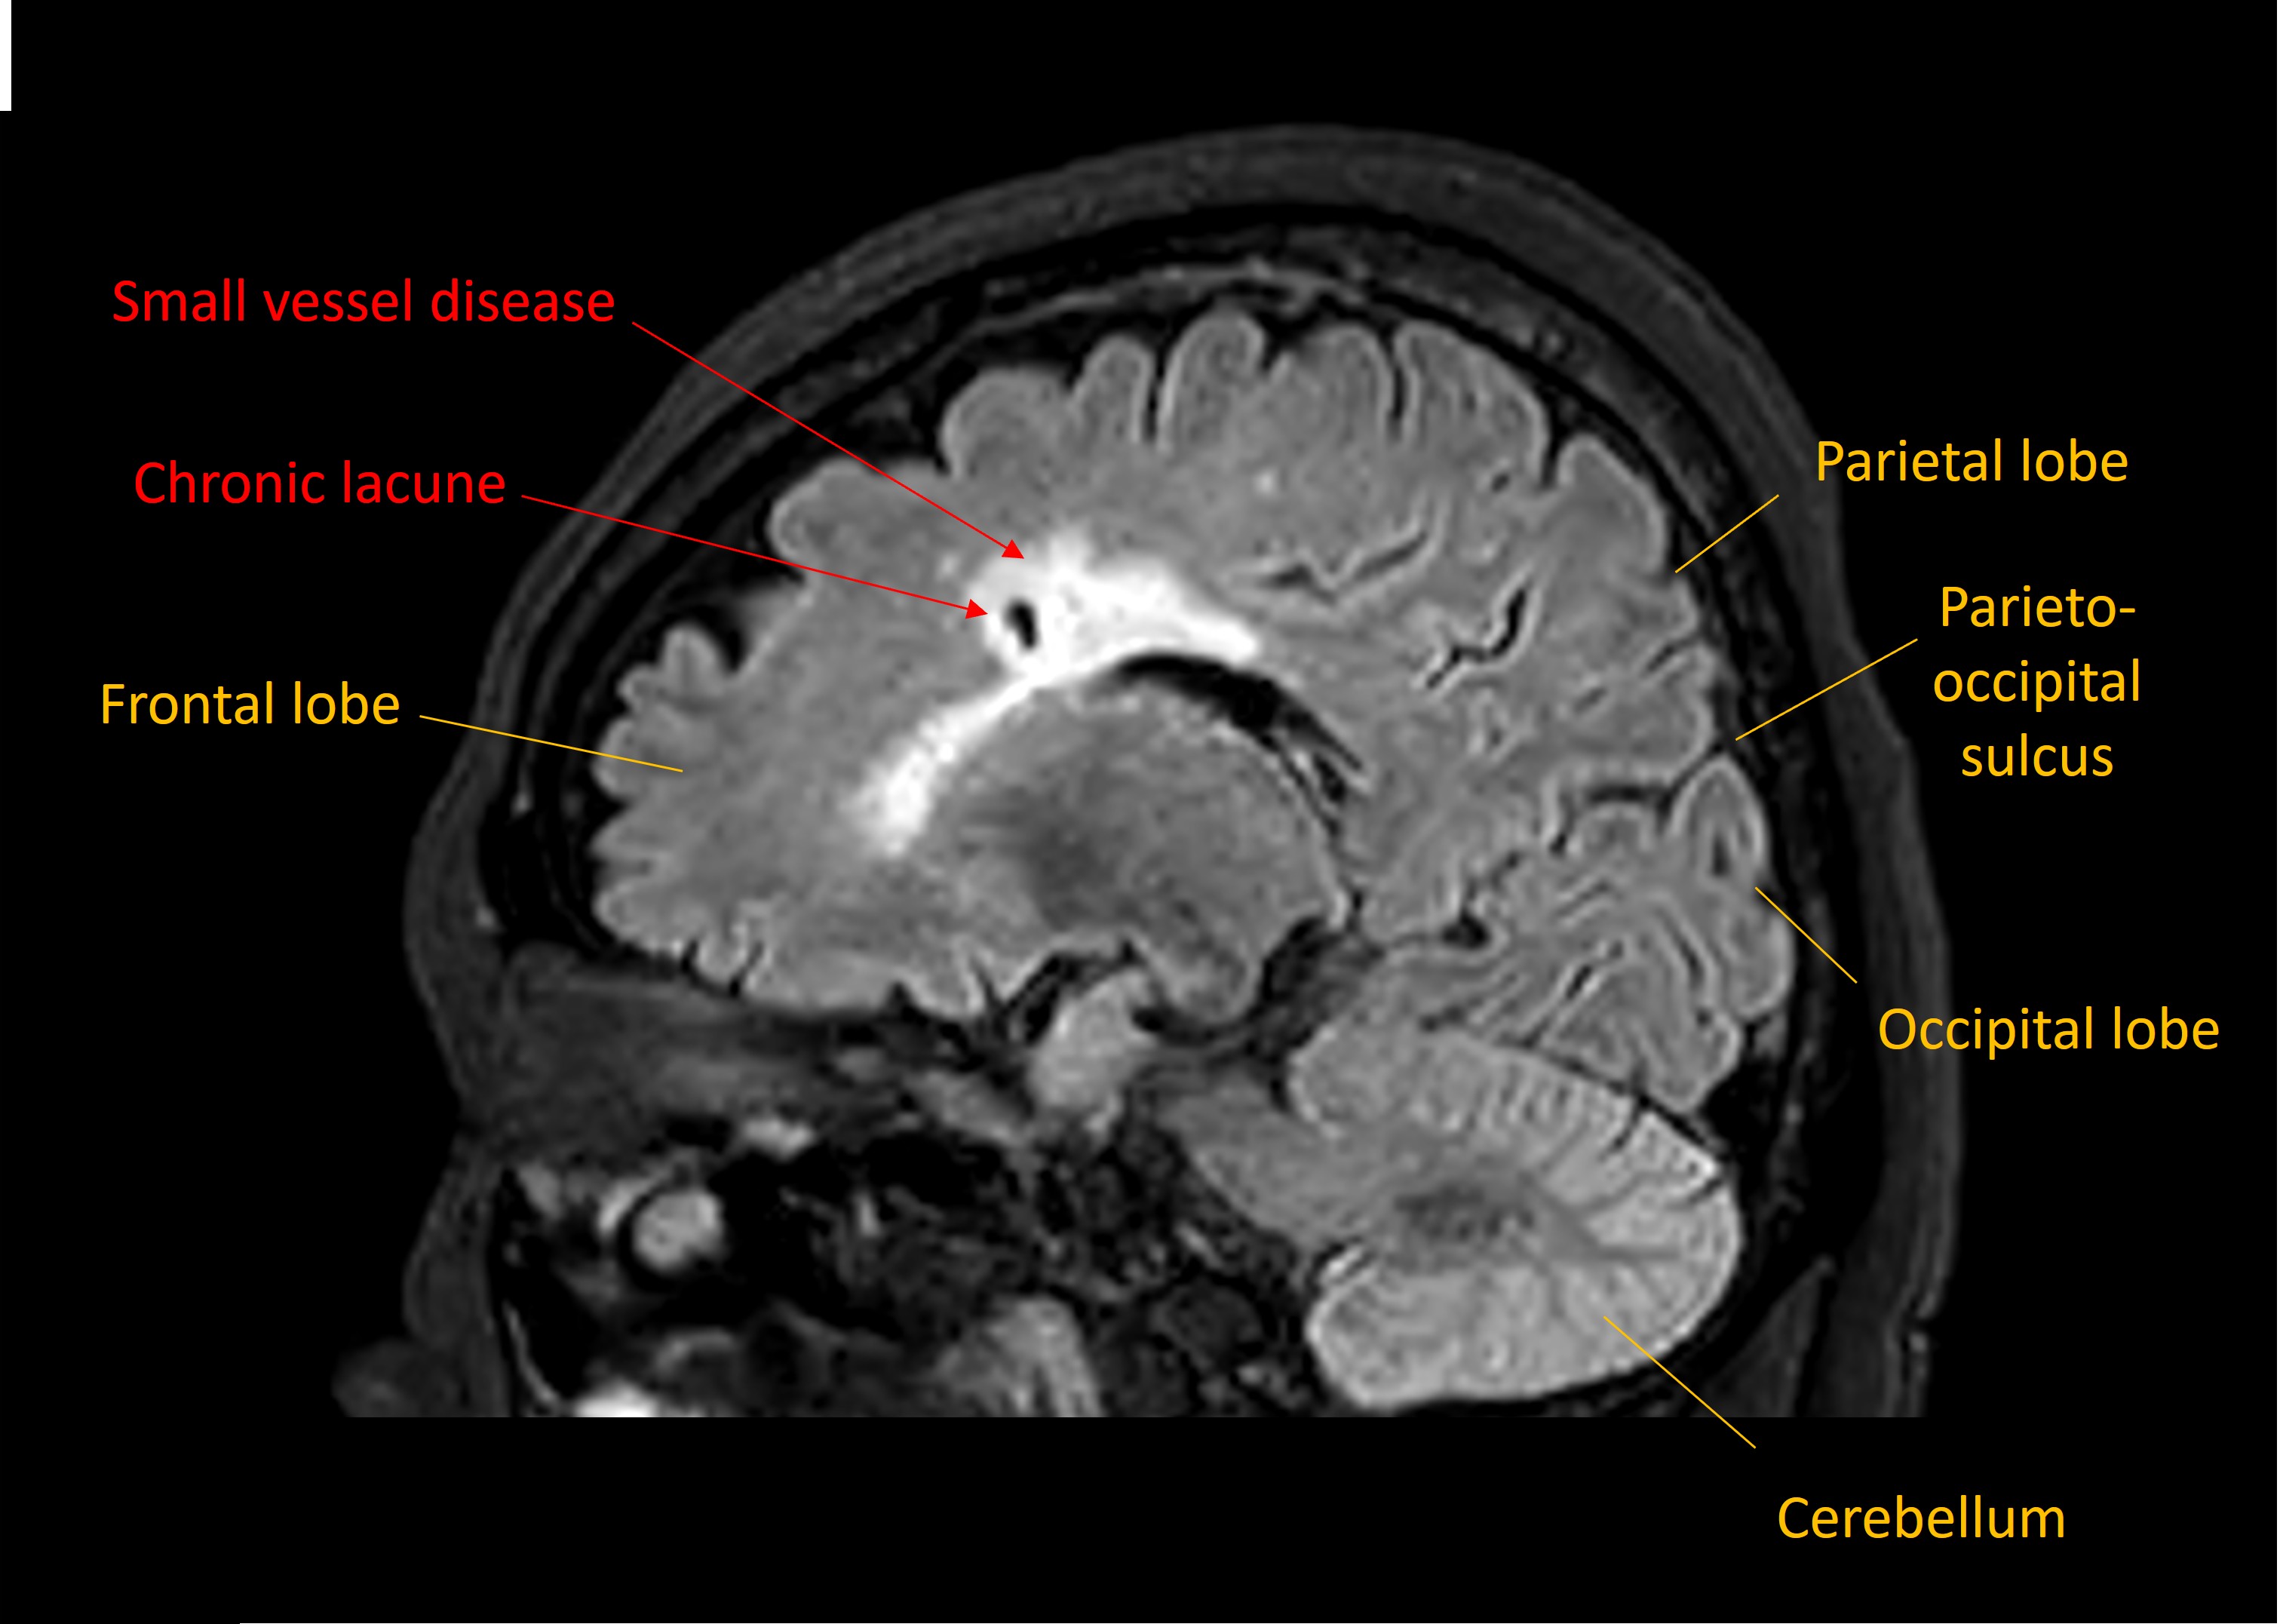

There was also evidence of severe small vessel disease changes and chronic clinically-silent lacunar infarcts, seen on the sagittal FLAIR sequence below.

MRI